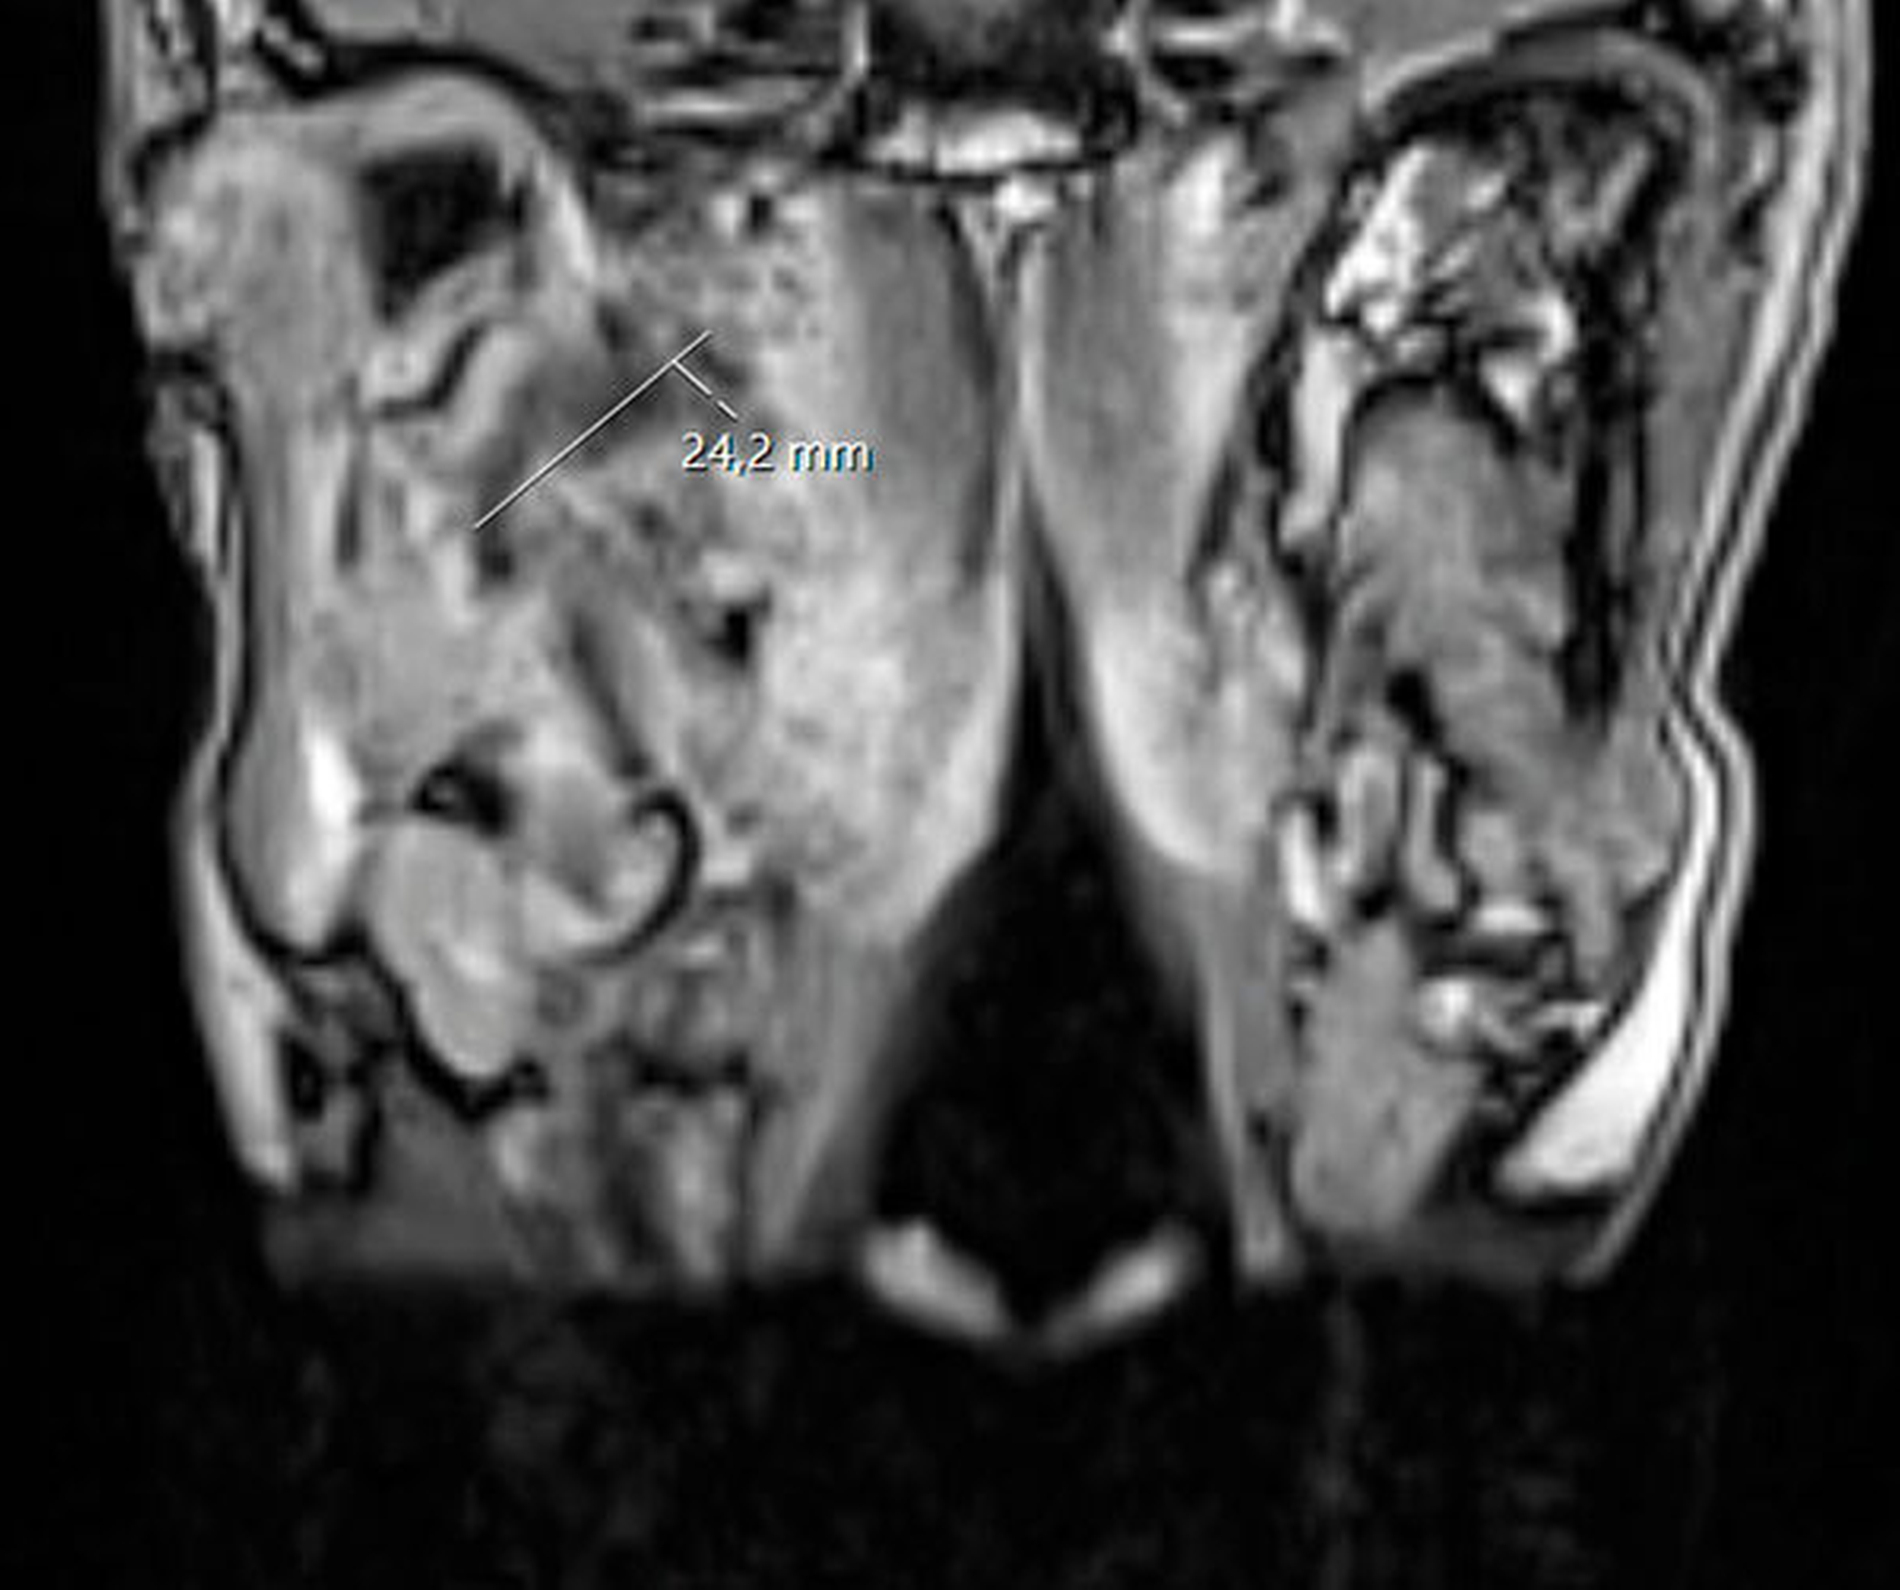

Unmittelbar nach der stationären Aufnahme wurde mit der intravenösen Antibiotikatherapie, Glukokortikoidgabe und antiphlogistischen Maßnahmen begonnen. Daraufhin zeigten sich die klinischen und die laborchemischen Entzündungsparameter rückläufig. Die Mundöffnung der Patientin war bereits am Folgetag mit einer Schneidekantendistanz von 40 mm deutlich verbessert. Zur Verlaufskontrolle und Beurteilbarkeit des Weichgewebes im Bereich der Mastikatorloge wurde am zweiten Tag nach stationärer Aufnahme eine Magnetresonanztomografie des Kopfes durchgeführt. Im Vergleich zur initialen Computertomografie der Halsweichteile zeigte sich eine zunehmende Resorption der liquiden ovalären Veränderungen in der rechten Mastikatorloge (Abbildungen 3 und 4). Zum Ausschluss einer otorhinolaryngologischen Pathologie wurde die Patientin konsiliarisch in der Hals-Nasen-Ohrenheilkunde der Universitätsmedizin Mainz vorgestellt. Die Kollegen fanden keine pathologischen Auffälligkeiten, so dass bei radiologisch rückläufigem Befund von einem Hämatom ausgegangen werden konnte. Am vierten Tag nach stationärer Aufnahme konnte die Patientin die Klinik mit nahezu normwertigen Laborparametern verlassen und in die ambulante Nachsorge entlassen werden.